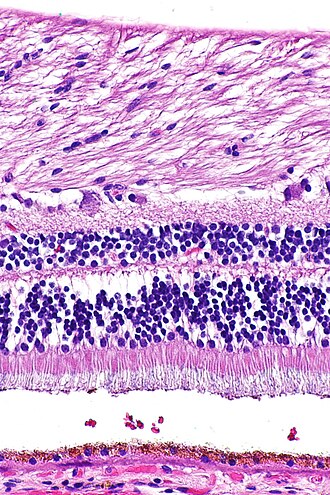

Hematoksilin-eozin bojilo ili HE bojilo je najčešće primjenjivana metoda bojenja u histologiji. Hematoksilin je bazično bojilo koja daje plavoljubičasto obojenje kiselim komponentama stanice, dok je eozin kiselo bojilo koja daje crveno-ružičasto obojenje bazičnim komponentama. Razlog zbog čega je baš ova metoda vodeća metoda bojenja već dugi niz godina je taj što se kombinacijom ovih bojila može obojiti cijela stanica i svi njezini dijelovi. Također, hematoksilin i eozin će dati takva obojenja koja se mogu lako razlikovati jedna od drugih što može uvelike pomoći u analizi i dijagnostici (McCann, 2015.). [1]

Eozin (prema grč. ἕως: zora, jutarnja rumen) je sjajnocrveno ksantensko bojilo, prvi put pripravljeno 1874. Eozin je kalijeva ili natrijeva sol tetrabromfluoresceina koji se dobiva adiranjem (dodavanjem) broma na fluorescein suspendiran u alkoholu. Mnogo se upotrebljavao u tekstilnoj industriji za bojenje svile i vune, a danas se koristi u fotografiji i kozmetici, za bojenje mikroskopskih preparata (zajedno s hematoksilinom), pripravu crvene tinte i drugo. [4] Eozin je ustvari naziv nekoliko fluorescentnih kiselih kemijskih spojeva koji se vežu i tvore soli s osnovnim, odnosno eozinofilnim spojevima poput bjelančevina koji sadrže aminokiselinske ostatke poput arginina i lizina, a boji ih tamnocrvenom ili ružičastom bojom kao rezultat djelovanja broma na fluorescein. Uz bojenje bjelančevina u citoplazmi, može se koristiti za bojenje kolagena i mišićnih vlakana za ispitivanje pod mikroskopom. Strukture koje se lako boje eozinom nazivaju se eozinofilnima. U području histologije, eozin Y je oblik eozina koji se najčešće koristi kao histološko bojilo. [5] [6]